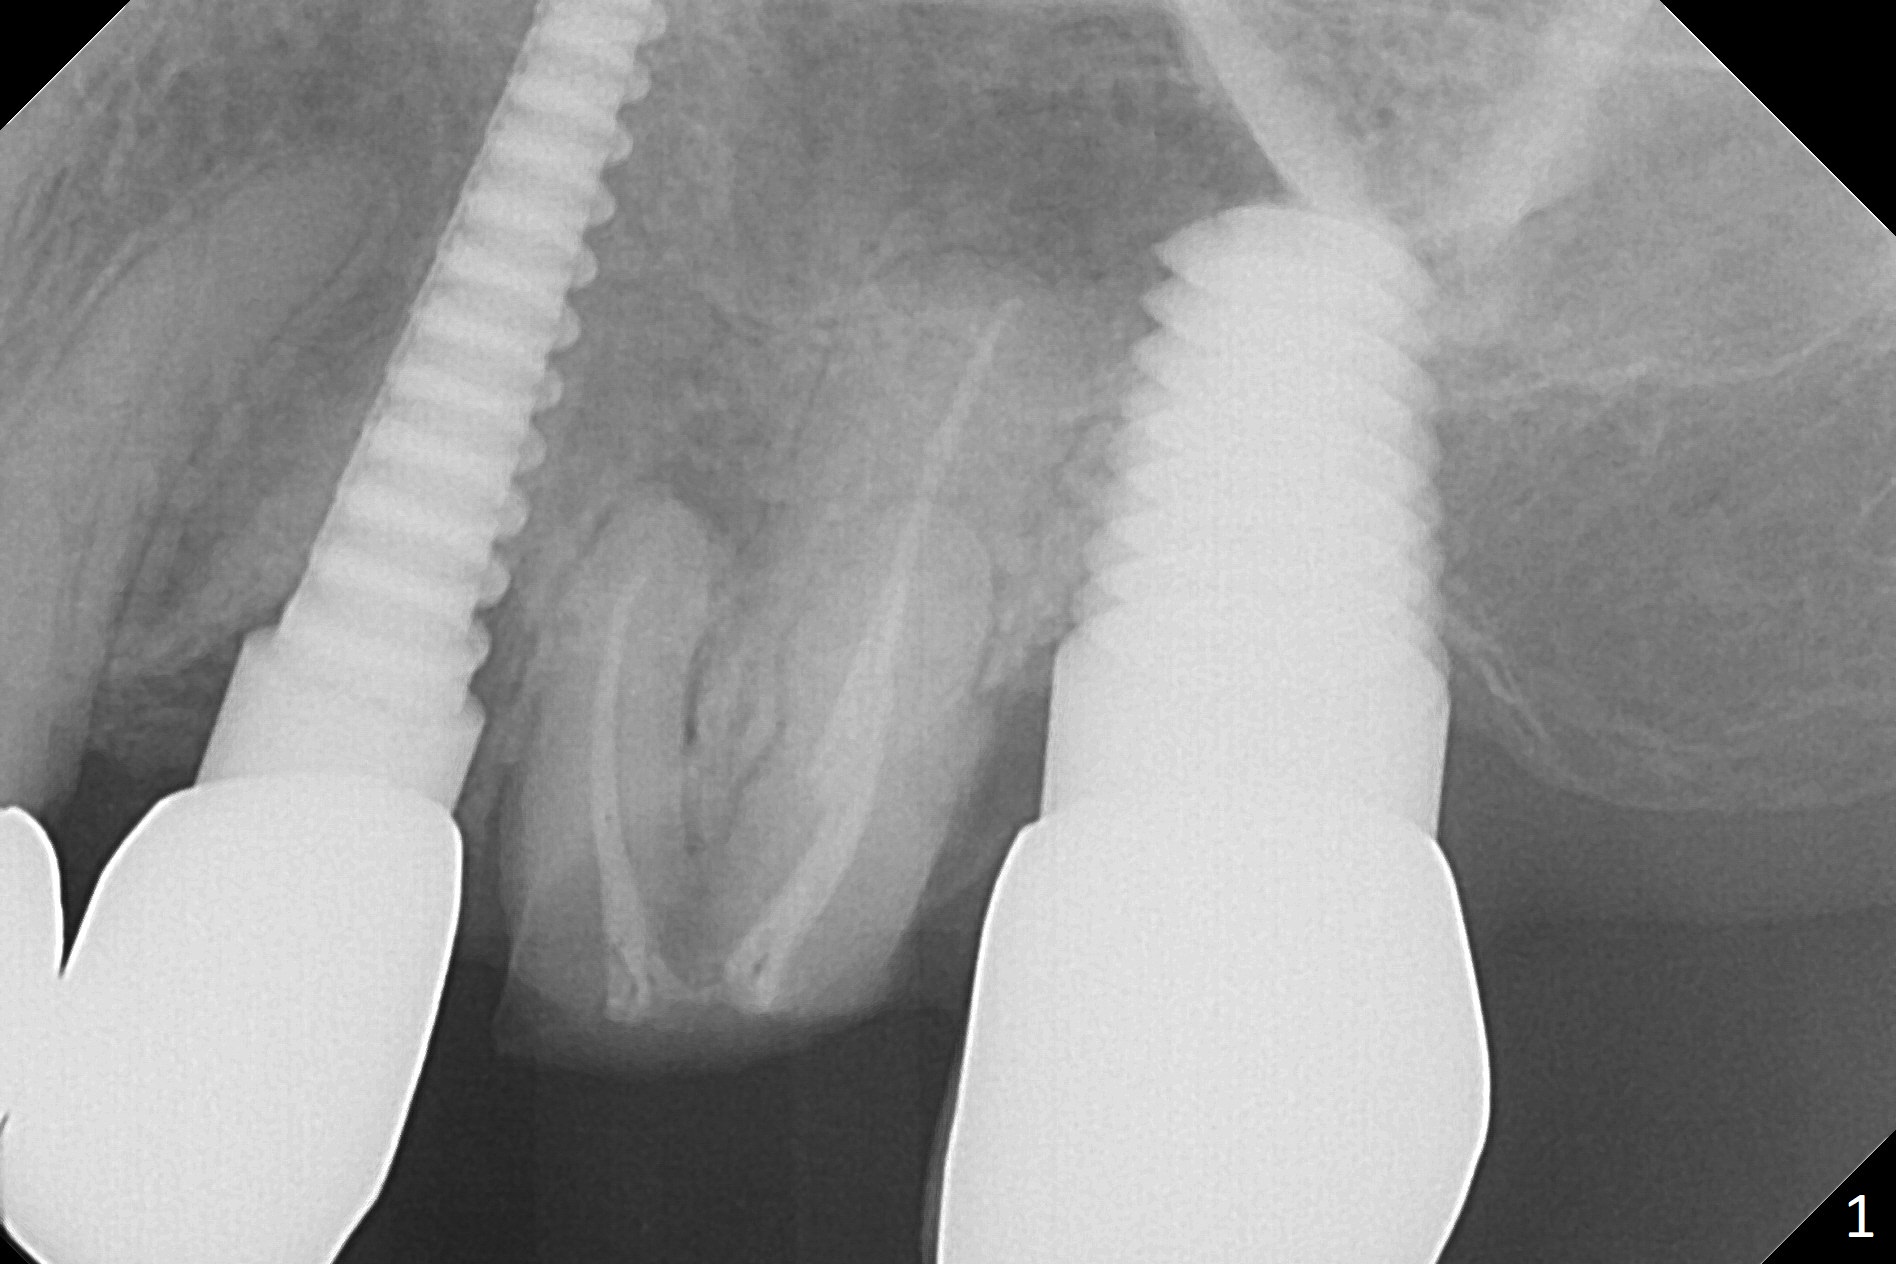

A 70-year-old woman fractures the crown at #14 (Fig.1).  A 5x11 mm implant will be placed at the septum (Fig.2).  Osteotomy depth can be determined using bony (Fig.3 with stopper) or gingival (Fig.4,5 with vision) landmark.  The CT was taken 5 years earlier.  Sagittal (Fig.6) and axial (Fig.7) sections confirm suitability of the 5x11 mm implant for the site.  Prepare surgical handpiece for sectioning the tooth for extraction.  After drills, use Magic Expanders for sinus lift.  Place Vanilla Graft prior to dummy implant(s).  A bone-level implant crown may be easier to be repaired if the proximal contact is not ideal.